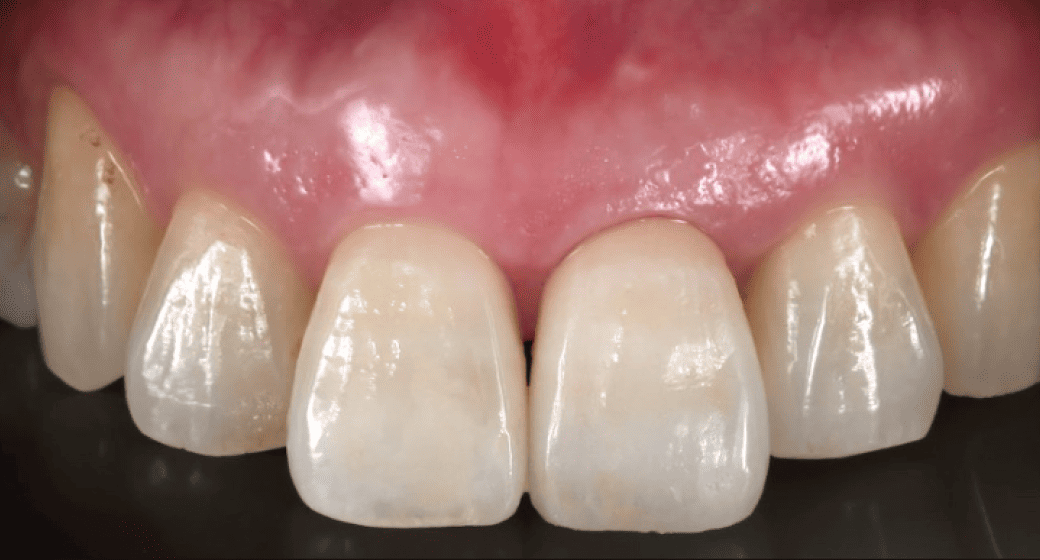

さらに、抜歯直後の歯ぐきの形を活かせるため、特に審美性が求められる前歯部では、自然な仕上がりが期待できるという利点もあります。歯がない期間を極力短くできるため、見た目や会話などに不安を抱える方にも安心してお選びいただけます。